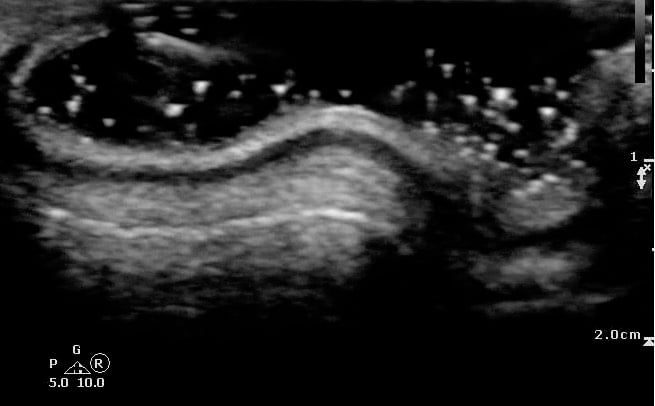

- Figure 1 and 2. Normal Ear

Video 1. Normal Ear - Anterior and posterior skin layers have thin hyperechoic appearance.

- Middle layer containing cartilage appears as a thin hypoechoic band.

- Normal Cartilage: